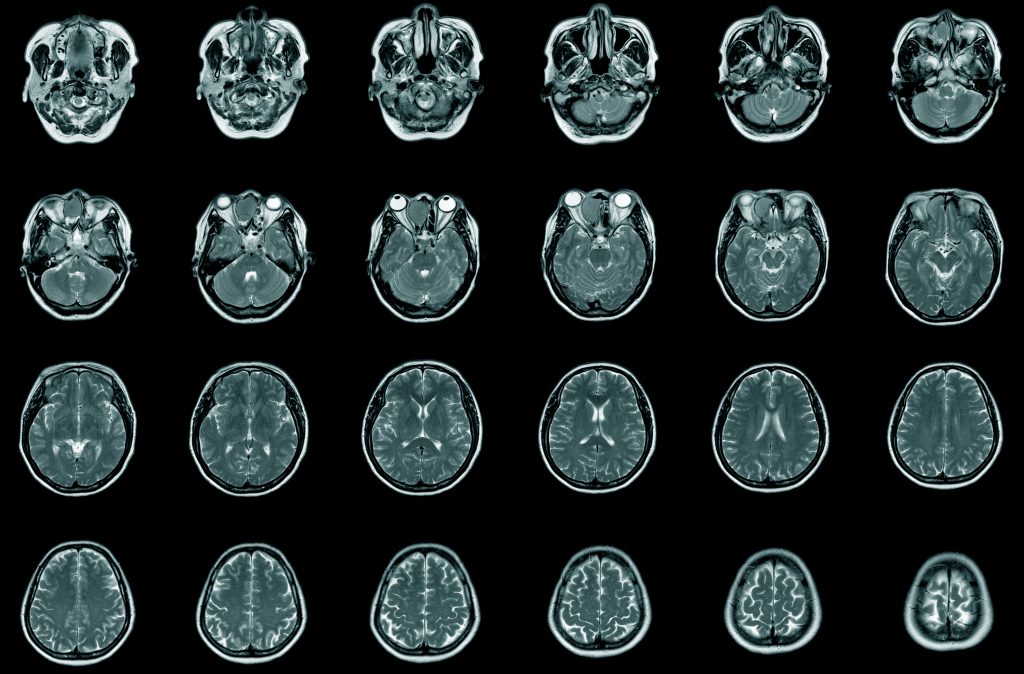

Current research on the action and effects of psychedelic compounds on brain function is driven by advancements in brain imaging technologies such as functional Magnetic Resonance Imaging (fMRI). These neuroimaging technologies allow researchers to observe the functional changes occurring within the brain during a psychedelic experience by measuring and mapping changes in blood flow within anatomical regions of the brain. Medical knowledge of the specific functions and specializations within different brain regions, combined with measurable changes in blood flow and neural activity, provides researchers with essential data needed to further assess and understand the physiological mechanisms and psychopharmacological effects of psychedelic compounds within the brain.

In addition to the objective and quantifiable data that psychedelic fMRI studies provide, research subjects can communicate the subjective effects of a psychedelic experience in real-time. This concurrent approach to gathering data allows researchers to identify potential associations and causal relationships between the qualitative patient experience and the quantitative empirical data. Another benefit of psychedelic research using fMRI and neuroimaging technologies is that they allow researchers to capture, map, and measure brain function at multiple time points. This provides researchers the opportunity to compare and contrast psychedelic effects on brain functionality over time, generating important data on functional brain changes pre-intervention and at multiple time points post-intervention.